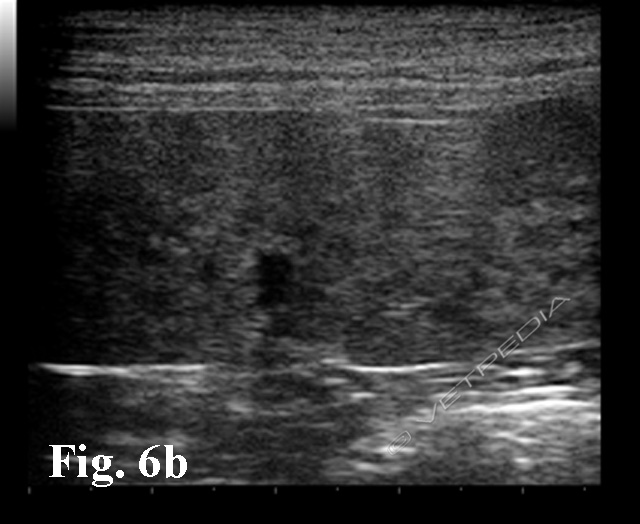

La durata del periodo di incubazione è altamente variabile in base al ceppo e alla specie interessata (generalmente da una a tre settimane). Occasionalmente possono verificarsi forme iperacute caratterizzate da tempi d’incubazione più brevi. I sintomi precoci della malattia sono febbre e disoressia cui seguono perdita di peso, anemia, trombocitopenia, splenomegalia, ittero, e soprattutto emoglobinuria, seguite da mialgie e talvolta dolore alla palpazione della loggia renale (segno del Giordano positivo) per l’effetto nefrotossico dell’emoglobina sui tubuli renali (Figg. 5, 6a e 6b; Video).